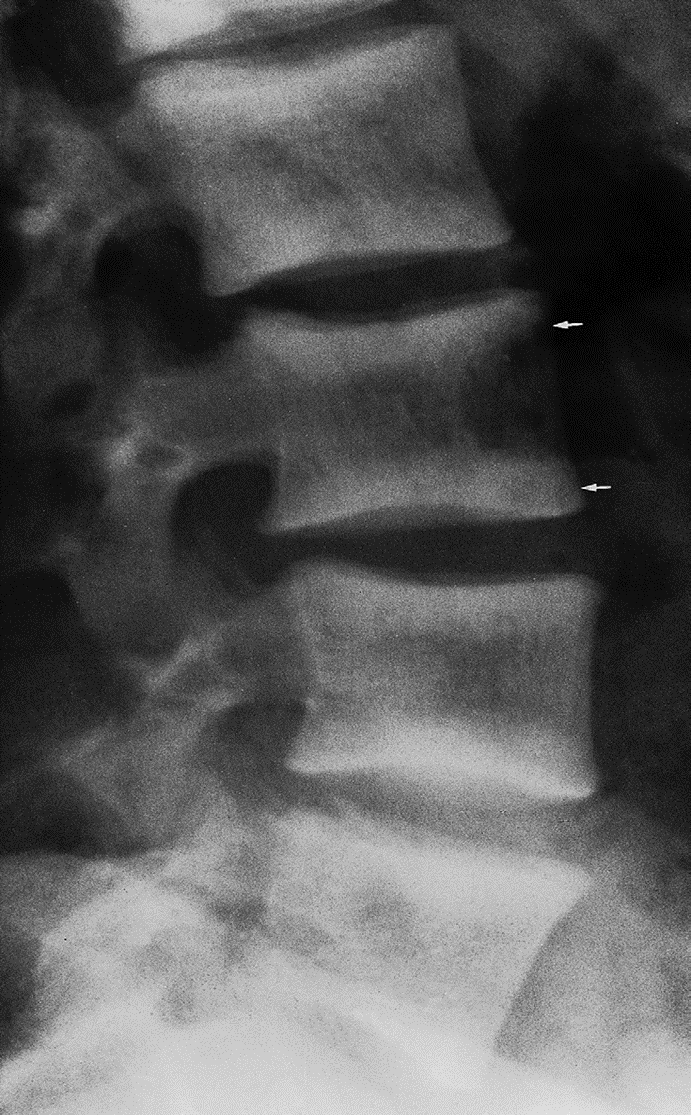

Ruger Jersey spine : secondary hyperparathyroidism z

Occurs due to renal failure/renal osteodystrophy prominent endplate densities at multiple contiguous vertebral levels to produce an alternating sclerotic-lucent-sclerotic appearance

On x-ray white margins with lucent central and vertical trabeculae, which is called( Ruger Jersey spine) these, (changes are due to renal dystrophy.

- Decreased bone density of the central portions (black area)

- Sclerotic vertebral end plates

(renal osteodystrophy). There are sclerotic bands running across the upper and lower ends of the vertebral bodies of the lumbar spine (arrows).